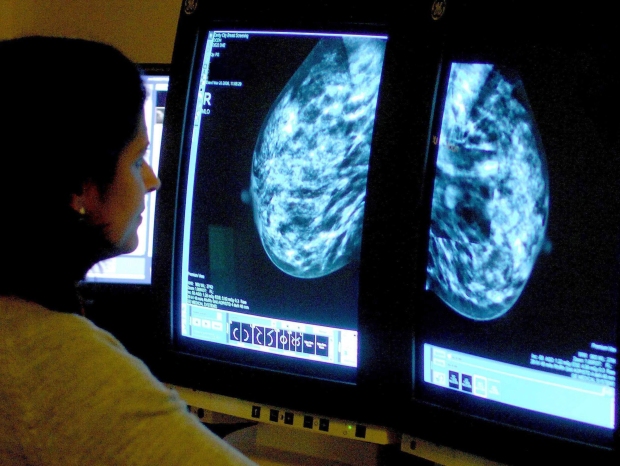

IA que prevê o risco de disseminação do câncer de mama pode salvar vidas, dizem especialistas.

Os cientistas desenvolveram um sistema para calcular o risco de propagação do câncer, procurando por alterações precoces nos gânglios linfáticos da axila.

Pode ser usado nos estágios iniciais da doença para mulheres com câncer de mama triplo negativo – cerca de 8.000 por ano.

Ao comparar os gânglios linfáticos de uma mulher com os de pacientes anteriores, a inteligência artificial pode descobrir o que um câncer provavelmente fará a seguir.

A inventora Dra. Anita Grigoriadis, do King’s College London, disse: “Pegamos essas descobertas sob o microscópio para criar um modelo de IA para potencialmente ajudar os médicos a tratar e cuidar dos pacientes.

A Dra. Grigoriadis testou sua inteligência artificial em mais de 5.000 gânglios linfáticos – glândulas do sistema imunológico – doados de 345 pacientes reais com câncer de mama.

O estudo, revelado no Journal of Pathology, descobriu que o algoritmo poderia prever o risco de disseminação com base nas respostas imunes nos gânglios linfáticos.